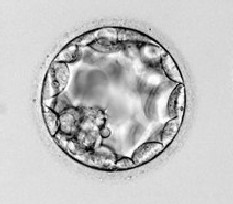

Embrionul va deveni un blastocist prin formarea unei cavitati umplute cu lichid.In acest stagiu,celulele se vor diferentia intre ele.Unele vor deveni cele destinate formarii fatului(celule din interior,vazute ca un mic palc in dreptul orei 7)si cele ce vor deveni placenta si membranele amniotice.(tropectoderma si celulele perimetrice).

EN este intrupata in acest moment in proportie de 55%.

Ziua 6

Blastocitul va migra din zona pelucida pentru a se implanta in uter.Aceasta se va intampla dupa ce embrionul a fost transferat in uter.

EN este intrupata in acest moment in proportie de 65%.